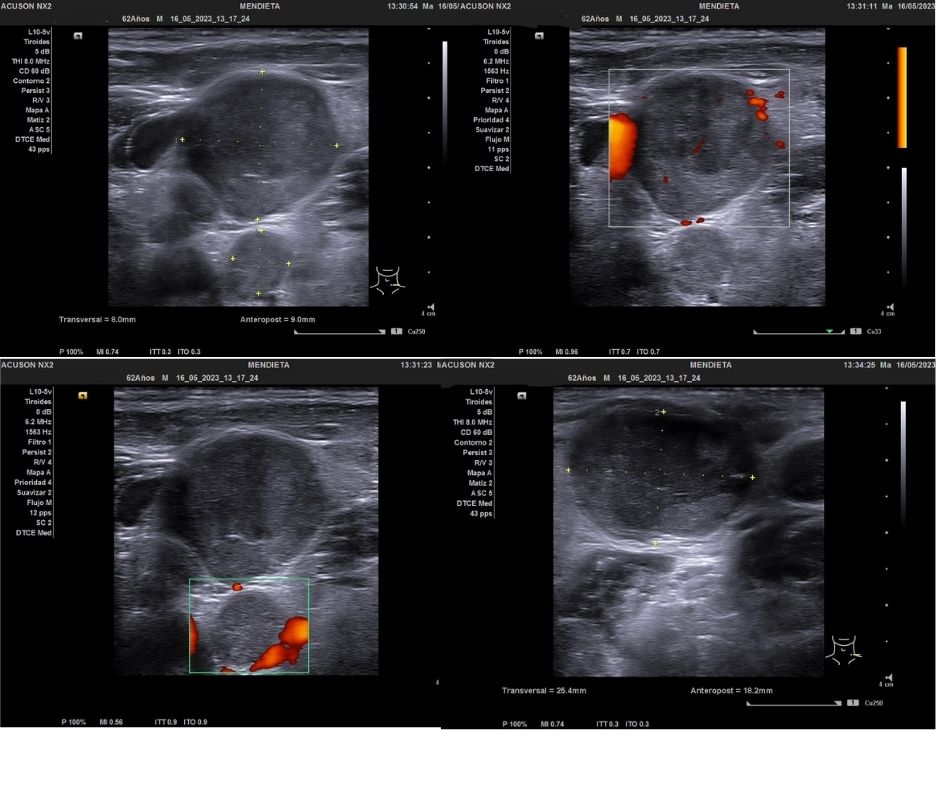

Ecografía cuello: Múltiples imágenes hiporecogénicas, heterogéneas que captan al Doppler color compatibles con adenopatías patológicas.